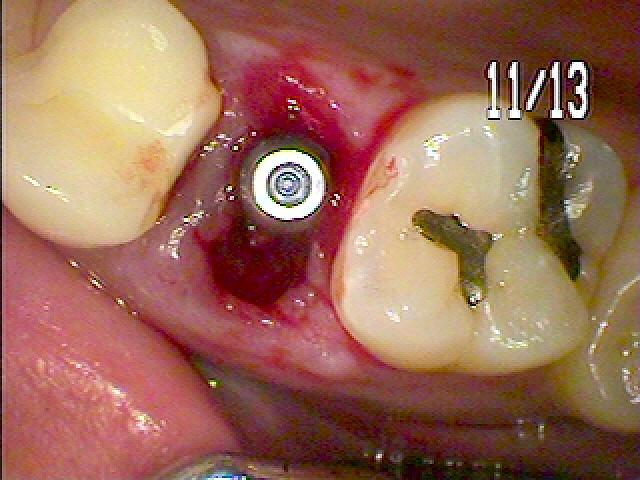

口蓋側へ埋入しています

口蓋側へ埋入しています